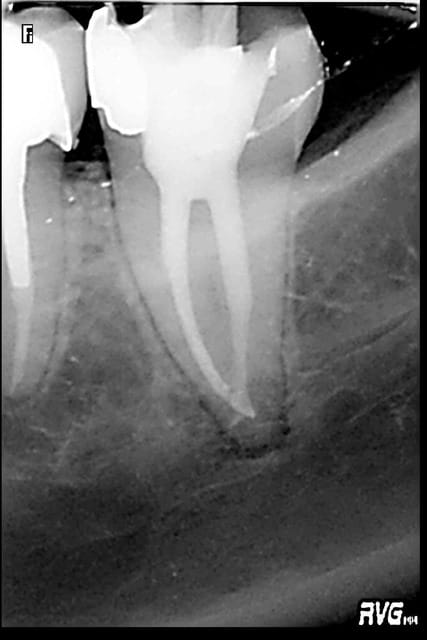

15/04/2011 à 21h44

premiere molaire au réciproc, bonnes sensations

R24 azxbz3 - Eugenol